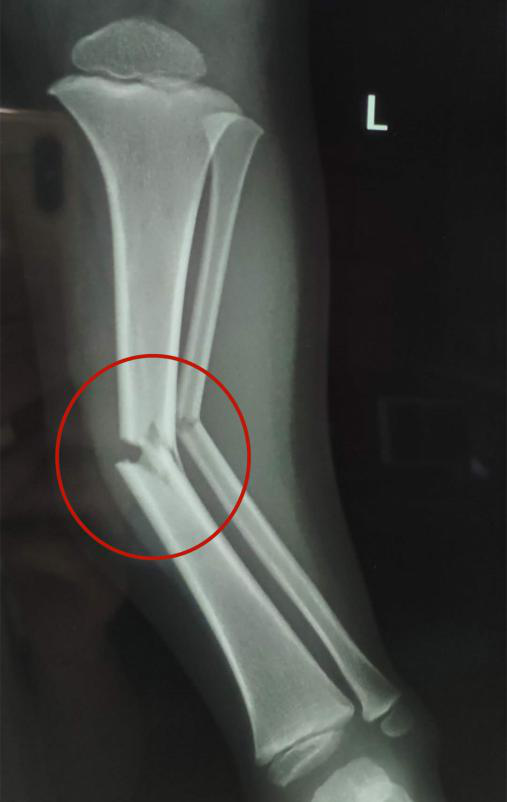

復(fù)位后,經(jīng)再次照X光顯示,患兒左下肢脛腓骨斷端緊密對(duì)合,外觀畸形得以糾正,手法復(fù)位治療非常成功。

手法復(fù)位后X片顯示脛腓骨斷端嚴(yán)密對(duì)合,左下肢中段畸形糾正